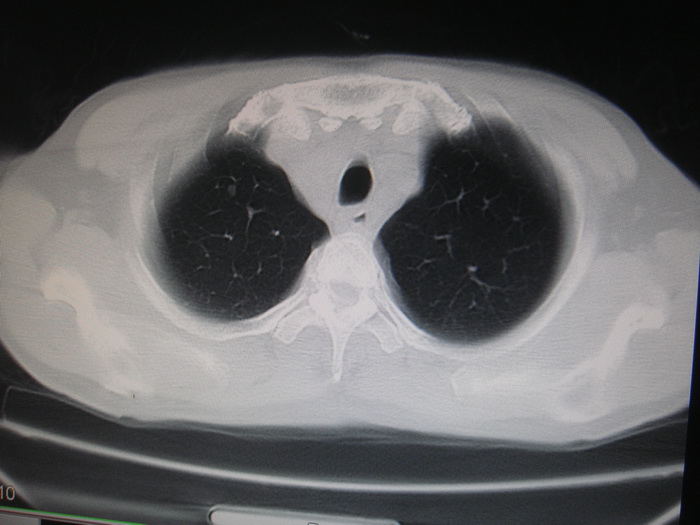

标题: CT28366:男性,45岁,偶尔发现右颈部肿块行胸部CT扫描。 [打印本页]

男性,45岁,偶尔发现右颈部肿块行胸部ct扫描。

两肺多发结节灶及纵膈淋巴结肿大考虑为转移

两肺多发性转移瘤,纵隔淋巴结转移。

两肺多发性转移瘤,纵隔淋巴结转移。食道中上段管壁似乎增厚,作相关检查。

两肺多发性转移瘤,前上纵隔淋巴结转移。